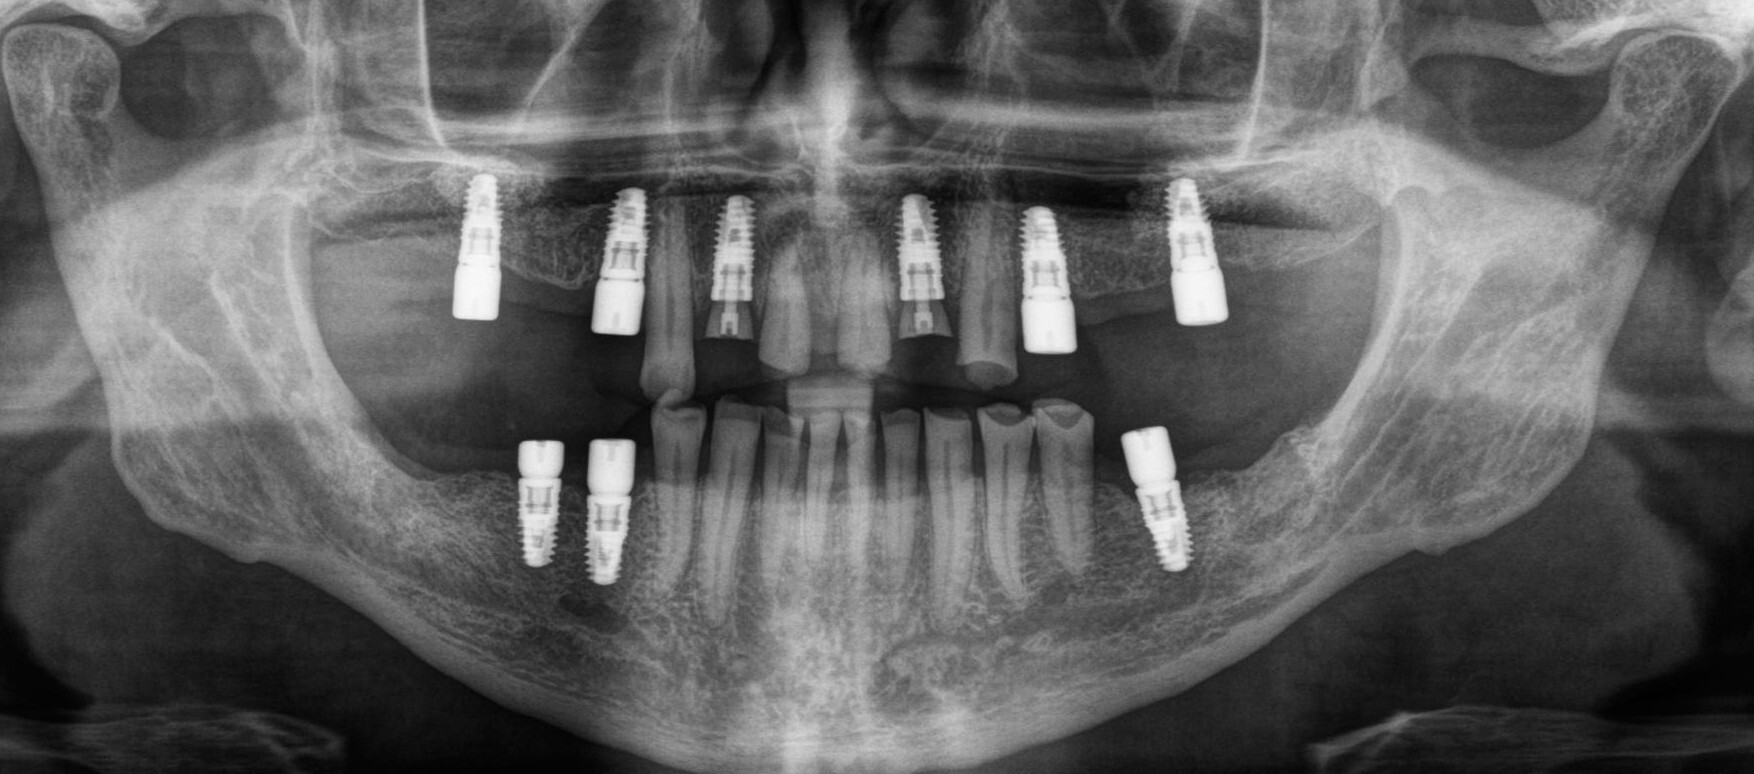

Дабы не перегружать вас обилием одинаковых картинок, я оставлю один рентгеновский снимок, но отмечу, что установка имплантатов на верхней и нижней челюсти проводилась с разницей в 10 дней.

На верхней челюсти было дополнительно удалено два боковых резца с одномоментной установкой имплантатов, так же они были установлены в области четверок и шестых зубов. Дополнительно было проведено наращивание костной ткани - двусторонний синус - лифтинг. О том, что это такое, можно почитать ТУТ и ТУТ.

Контрольный рентгеновский снимок: